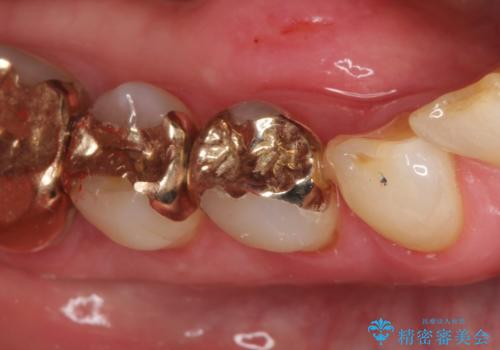

【セラミックインレー】虫歯になった詰め物部分を修復

- 前医で治療された詰め物の部分に、定期検診で虫歯が見つかったため、セラミックインレーにて修復治療を行いました。

接着時にはラバーダム防湿を行っています。